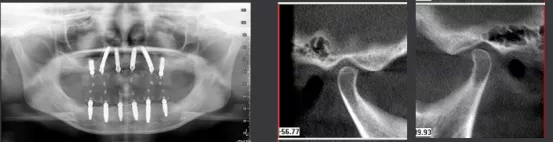

影像学检查

· 缺牙区骨量尚可,余留牙骨吸收至根尖1/3 。

· 双侧髁突骨皮质连续。

· 头影测量分析,临床诊断为:上颌前突,骨性二类错合畸形,上下中切牙及上下唇前突。

· 术后CBCT检查可见种植体植入位置佳,与术前设计一致。

· 修复体戴入后髁突位于关节窝内的适中位置。

· 植入精度分析,误差较小。

· X线片显示,种植体周骨稳定性、关节髁突位置评估均无异常。